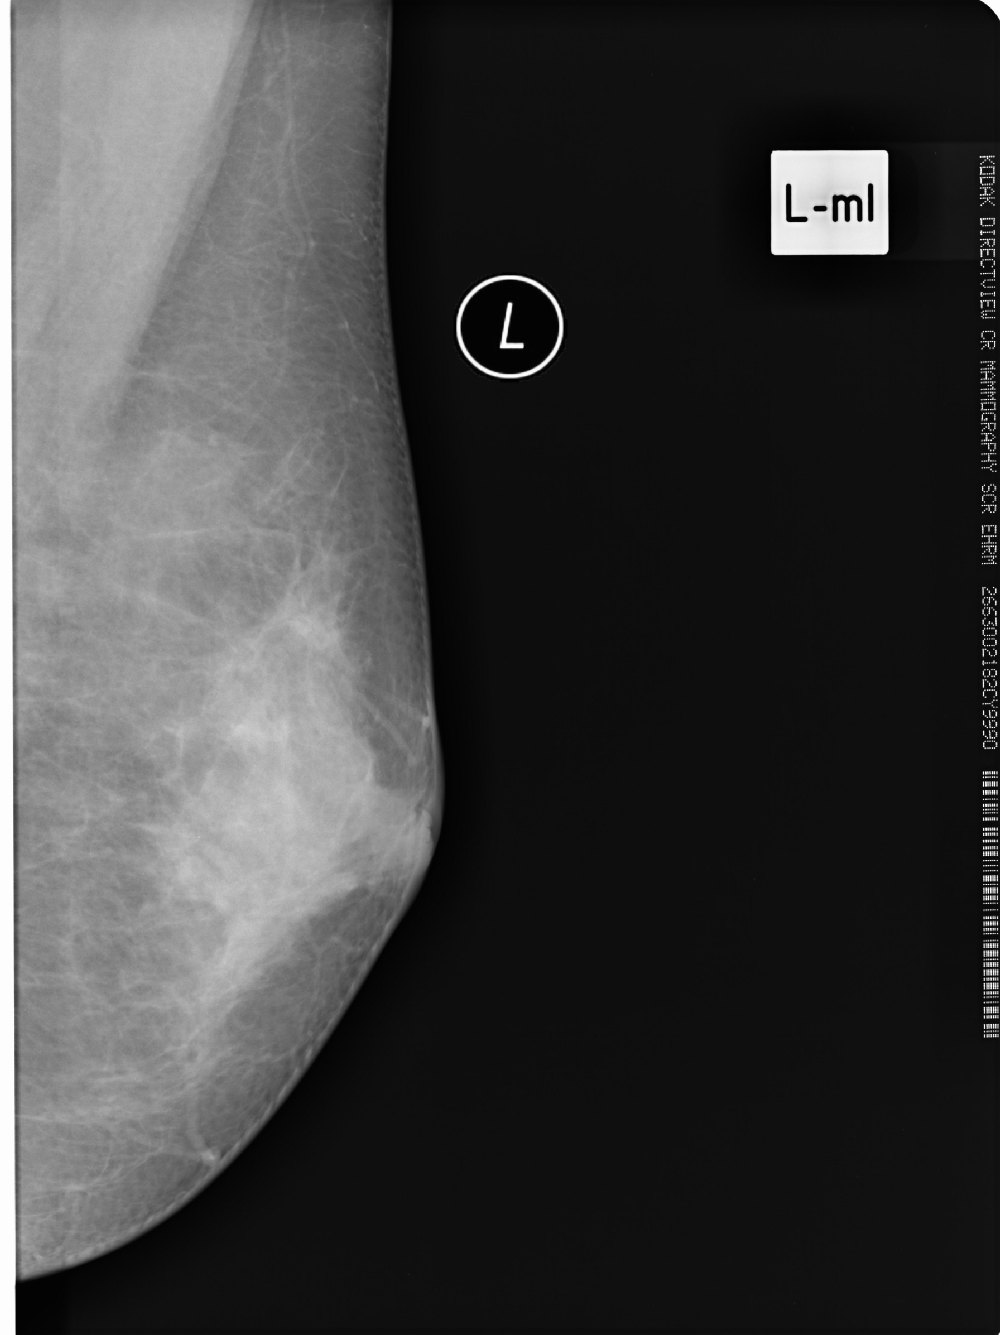

标题: X6857:女,39岁,右乳肿块半年余;三天后公布结果。 [打印本页]

标题: X6857:女,39岁,右乳肿块半年余;三天后公布结果。

左侧乳腺局部不对称性密度增高,局部可见纠集征象,左侧乳腺癌不除外。

左乳腺体增生可能性大

x6857,女,39岁,右乳肿块半年余;病理结果。

“右”乳纤维腺瘤

纤维腺瘤诊断要点:1,40y以下青年女性2,类圆形肿块,边光、锐利,可有分叶,密度或信号均匀,部分可见粗颗粒样钙化3,增强多呈缓慢渐近性直均匀强化或离心样强化。